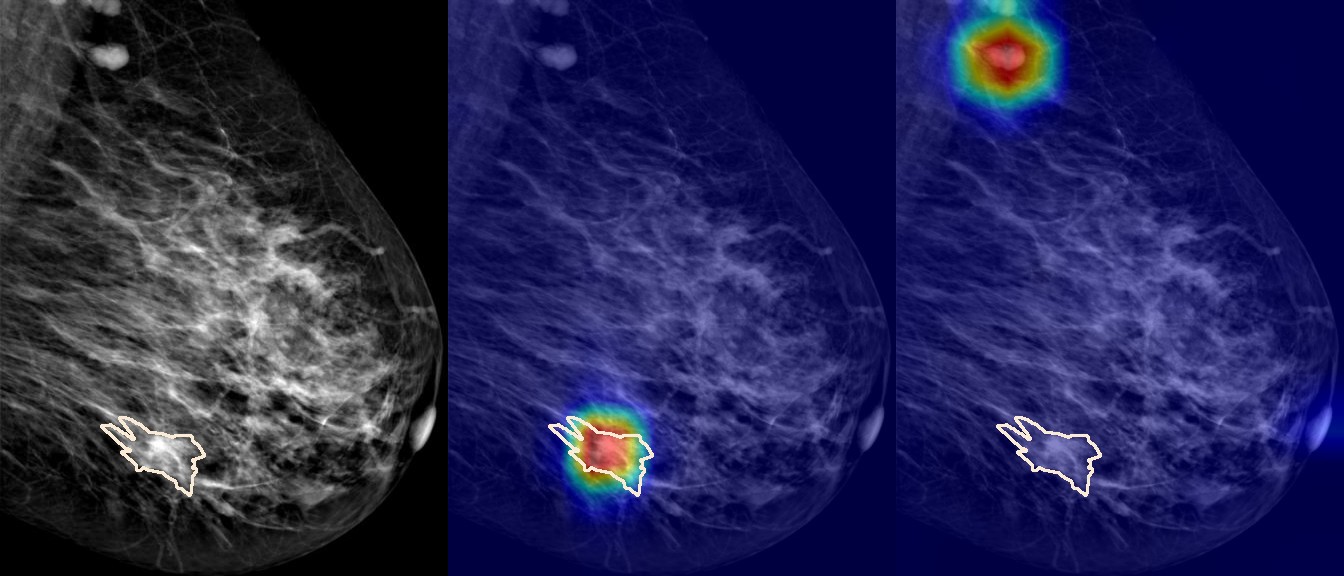

To interpret the decision-making process behind the quantitative results, we visualized Class Activation Maps (CAM) for the top-performing methods, ERM and VREx. Figures 1 through 2 illustrate discriminative regions identified by the models within the full mammograms.

Localization of Clinical Features: A key concern in medical AI is whether high performance stems from genuine pathology detection or spurious background correlations. Our visualizations suggest that Standard ERM achieves its superior quantitative performance by predominantly prioritizing clinical cues. As shown in the top rows of the Figure 1 and Figure 2, the ERM-trained models consistently focus attention on the specific lesion regions within the breast tissue. This demonstrates that despite lacking explicit invariance constraints, ERM is capable of learning robust, medically relevant features when trained on diverse multi-source data.

Attention Drift in Both Methods: While both ERM and VREx generally identify the correct region of interest in successful cases, neither method is immune to attention drift. We observe instances in both training paradigms where the model focuses on irrelevant areas, such as healthy fibroglandular tissue or background artifacts (e.g., rows 5 and 6 in Figure 1). This indicates that while VREx is designed to penalize instability, it does not guarantee perfect anatomical focus compared to the unconstrained ERM baseline.